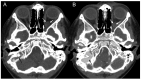

Results: A 6-year-old patient was admitted for right otomastoiditis and thrombosis of the sigmoid and transverse sinuses, as well as the proximal portion of the internal jugular vein. Radiological examinations revealed a left orbital mass (22 × 14 mm) compatible with asymptomatic orbital meningocele (MC) herniated from the superior orbital fissure (SOF). The child underwent a right mastoidectomy. After the development of symptoms and signs of intracranial hypertension (ICH), endovascular thrombectomy and transverse sinus stenting were performed, with improvement of the clinical conditions and reduction of the orbital MC. The systematic literature review encompassed 29 publications on 43 patients with spontaneous orbital MC. In the majority of cases, surgery was the preferred treatment.